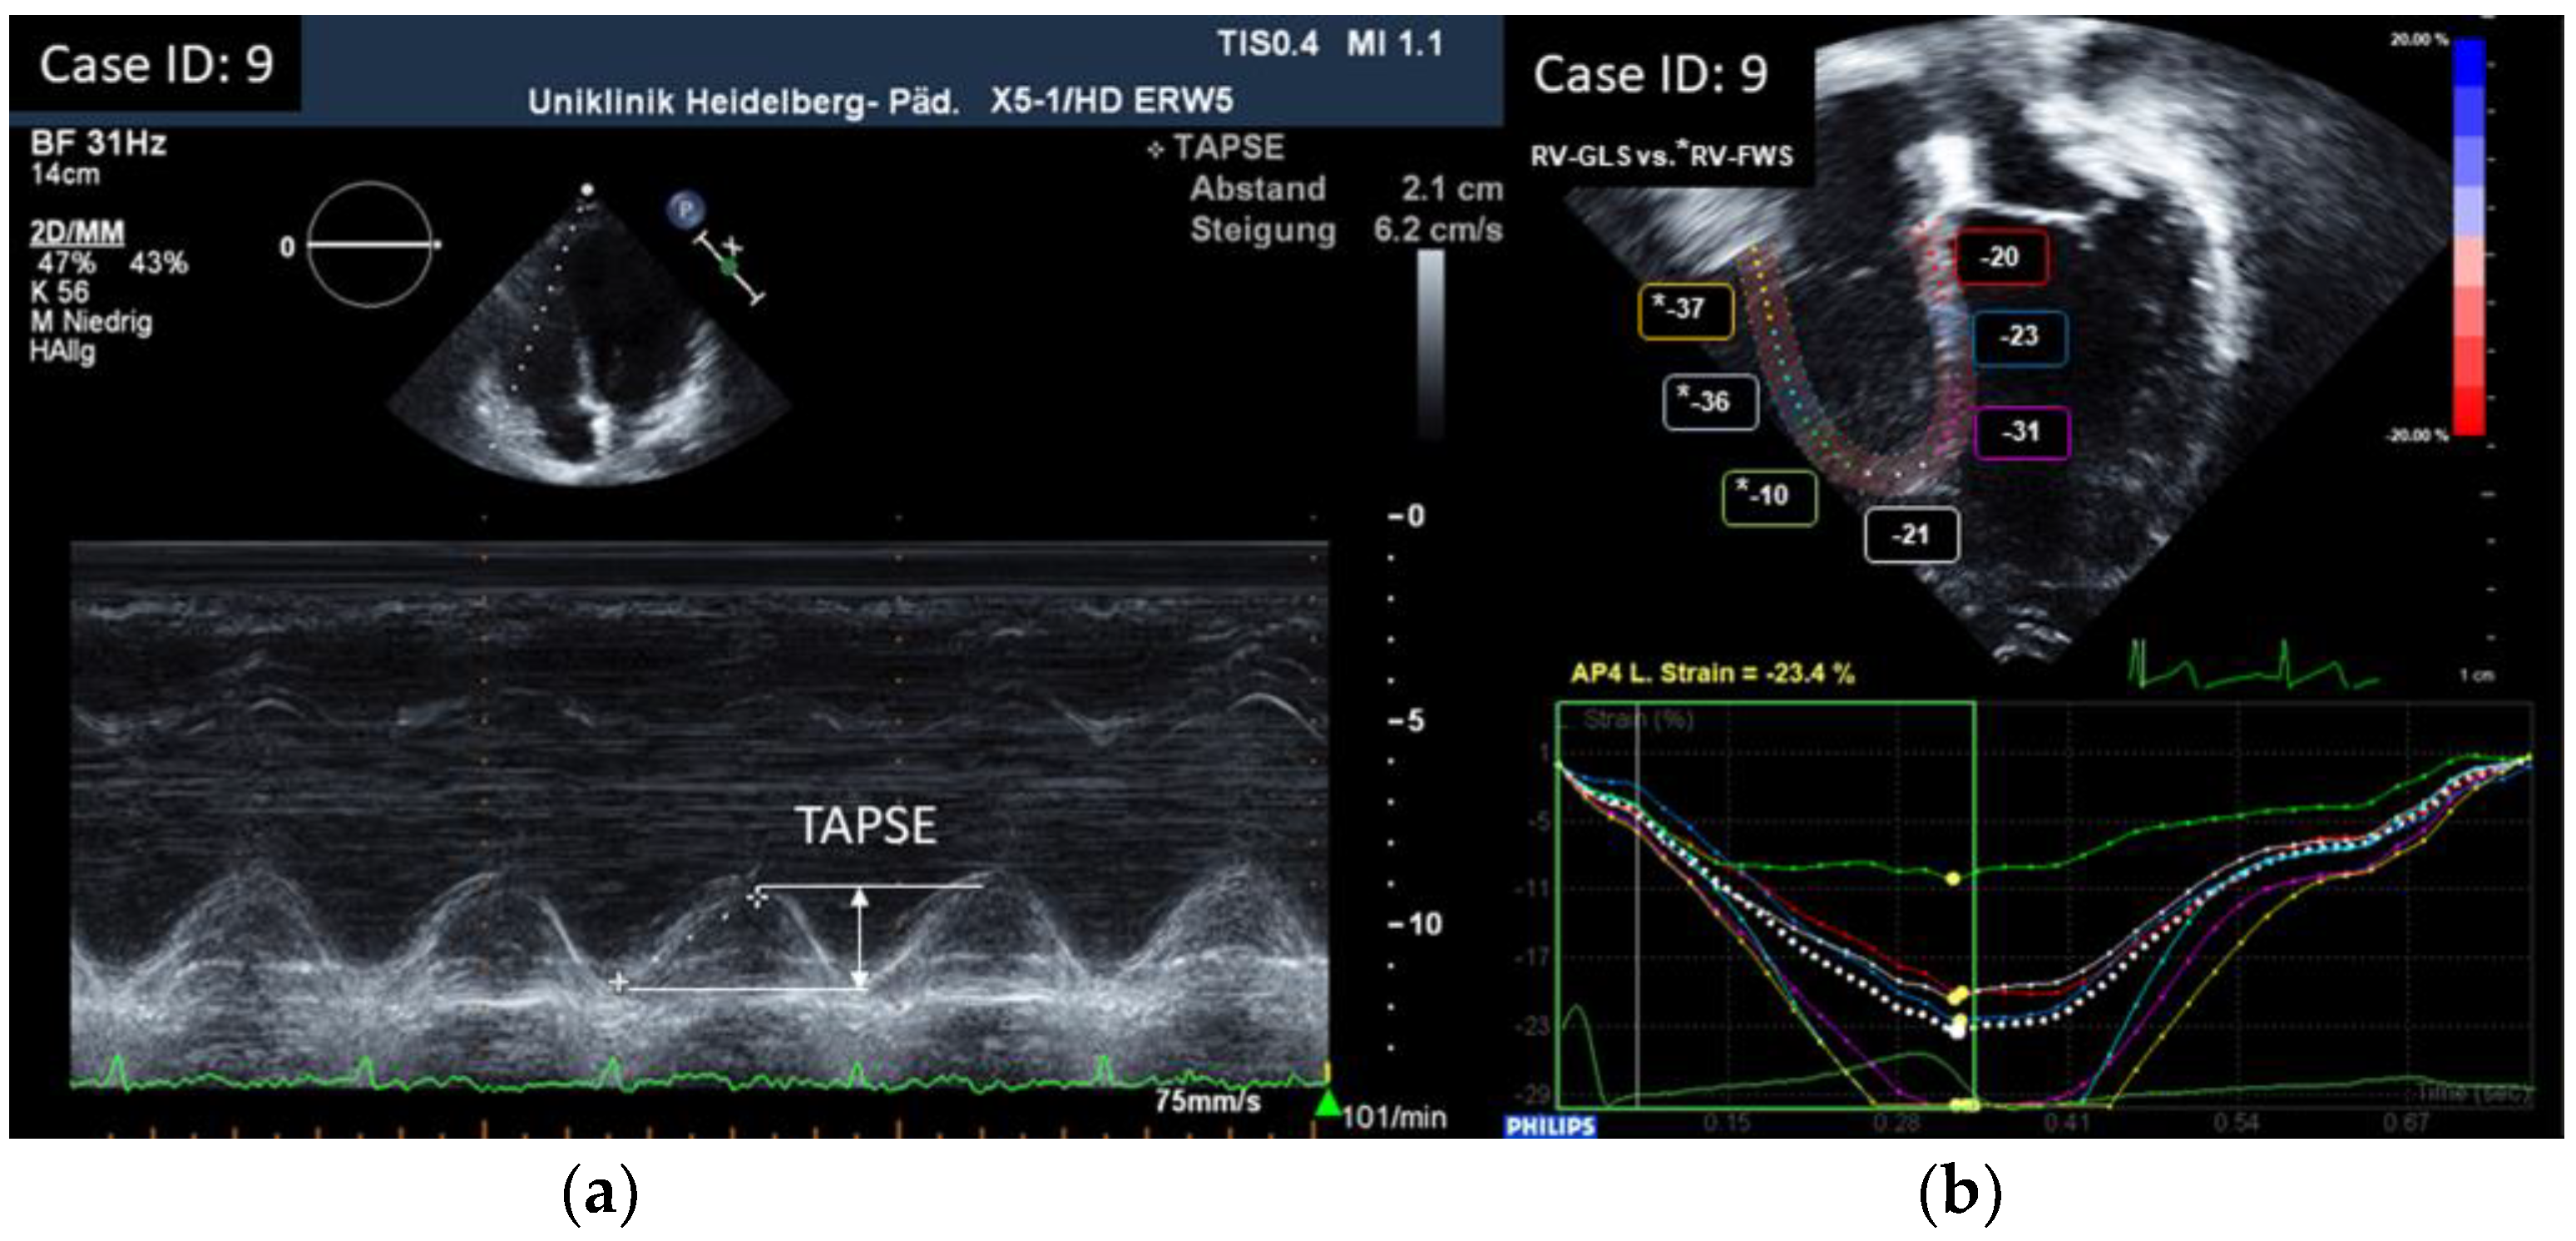

3.2. Results of Echocardiographic Measurements

| 9 | 2.1 | / | −27.7 | 14.5 | 42.2 | 0.29 | |